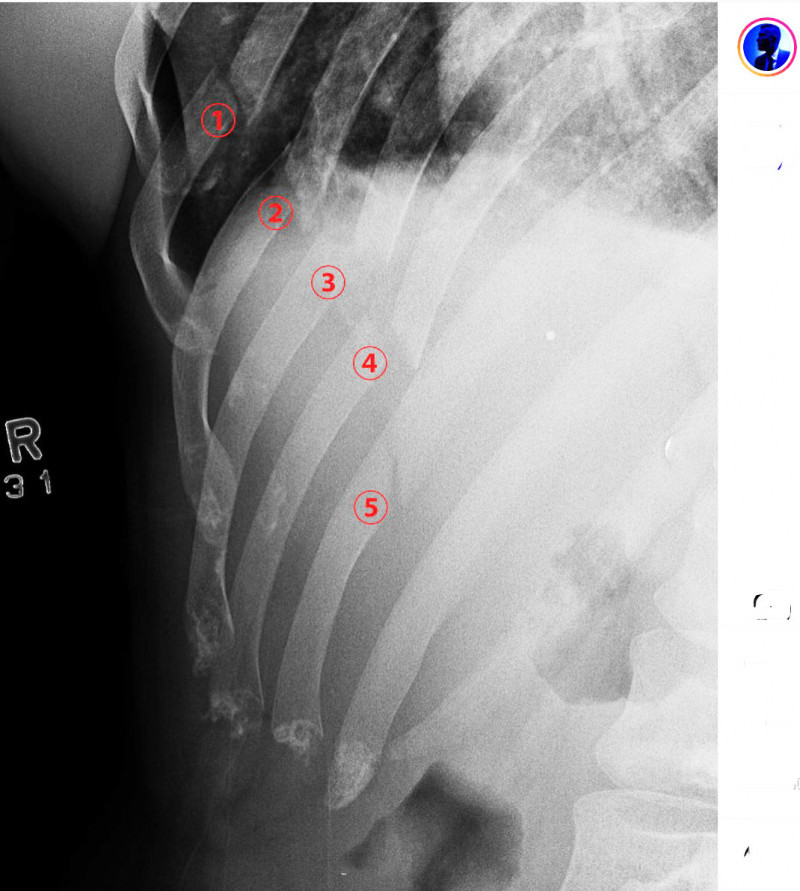

レントゲン写真、肋骨5箇所が折れている@blackeagle_170より